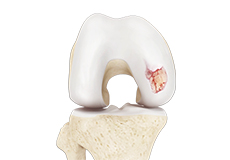

Chondral or Articular Cartilage Defects

The articular or hyaline cartilage is the tissue lining the surface of the two bones in the knee joint. Cartilage helps the bones move smoothly against each other and can withstand the weight of your body during activities such as running and jumping. Articular cartilage does not have a direct blood supply to it, so has less capacity to repair itself.

Osteochondral Defect of the Knee

An osteochondral defect, also commonly known as osteochondritis dissecans, of the knee refers to a damage or injury to the smooth articular cartilage surrounding the knee joint and the bone underneath the cartilage. The degree of damage may range from a rupture of the cartilage to a slight crack of the bone to a piece of the bone breaking off within the joint.

Articular Cartilage Injury

Patients with articular cartilage damage experience symptoms such as joint pain, swelling, stiffness, and a decrease in range of motion of the knee. Damaged cartilage needs to be replaced with healthy cartilage and the procedure is known as cartilage replacement.